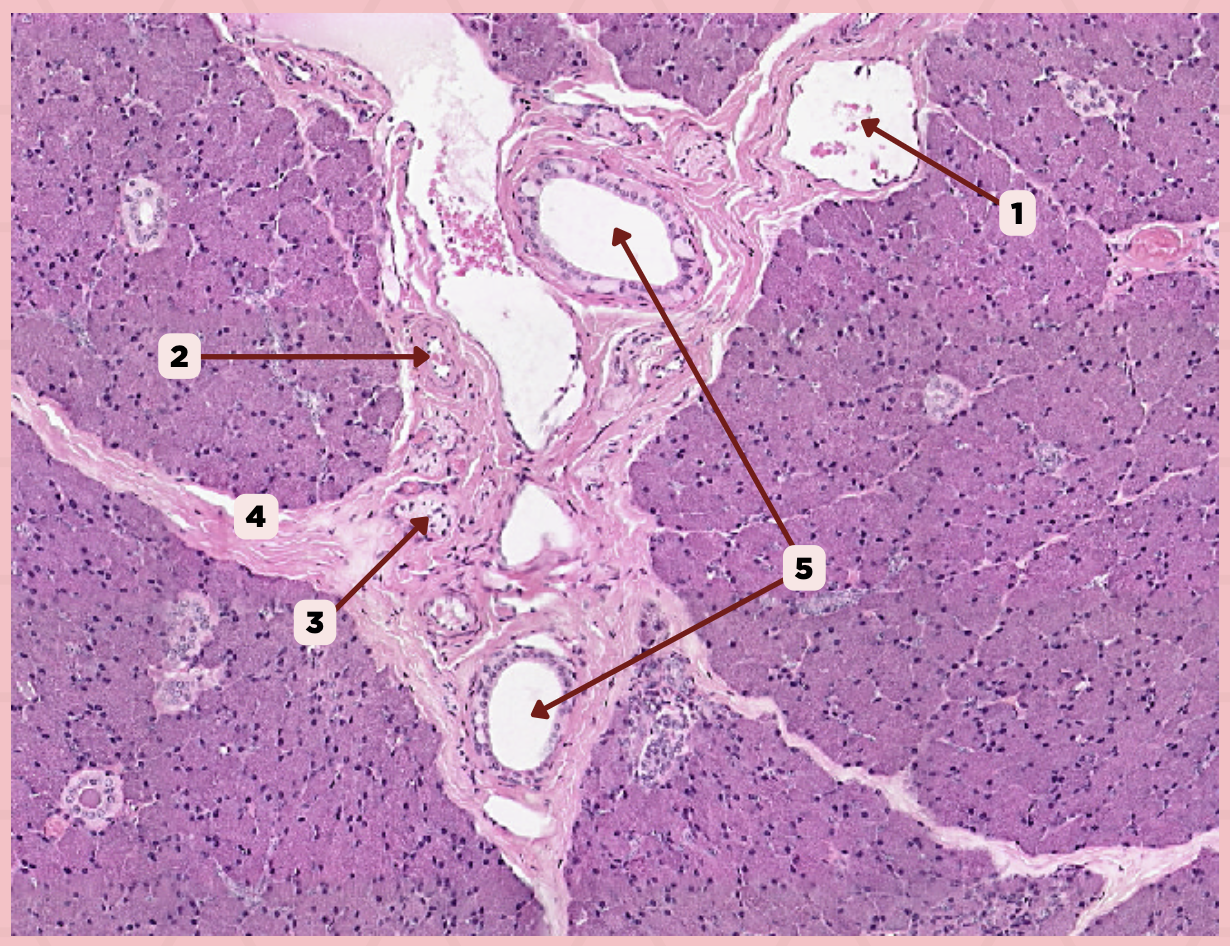

Parotid

Vein

Identify the structure labeled as 1.

Artery

Identify the structure labeled as 2.

Nerve

Identify the structure labeled as 3.

Interlobular Septa

Identify the structure labeled as 4.

Interlobular Duct

Identify the structure labeled as 5.